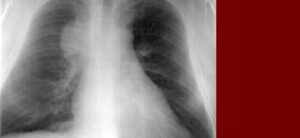

Криптогенная организующая пневмония (COP) — это идиопатическое заболевание легких, характеризующееся чрезмерным разрастанием грануляционной ткани в легких, блокированием просвета бронхов и альвеол, провоцирующим хроническое воспаление в прилегающих альвеолах. CUP относится к группе диффузных паренхиматозных заболеваний легких — облитерирующего бронхита с организуемой пневмонией. Термин «криптогенный» означает, что этиологический фактор развития заболевания неизвестен; это наиболее распространенная форма пневмонии. …